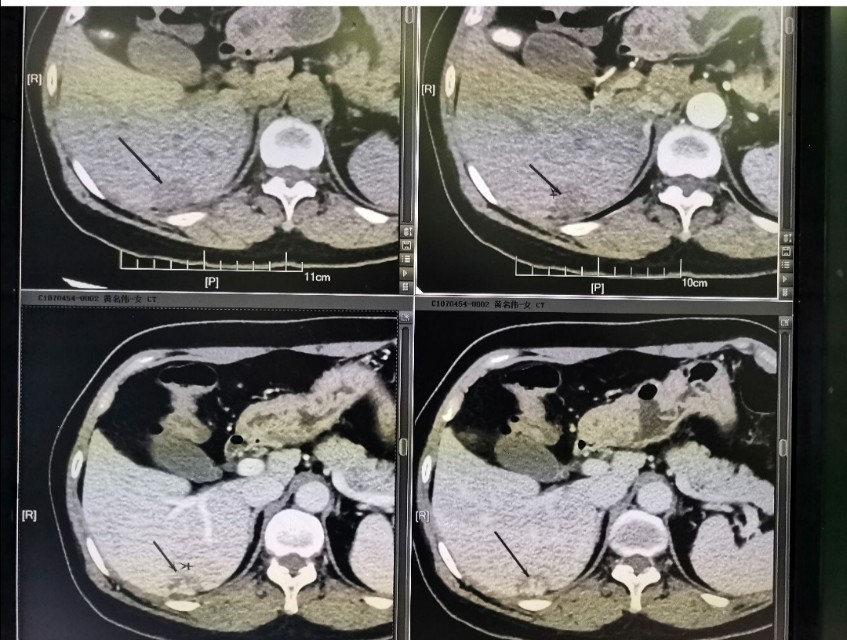

在CT平扫中, 肝血管瘤通常表现为圆形或卵圆形的低密度影 ,边界清晰。然而,这种表现并不具有特异性,因为其他肝脏病变也可能呈现类似的影像特征。因此,动态增强CT扫描成为诊断肝血管瘤的关键。

动态增强CT扫描通常包括动脉期、门静脉期和延迟期三个阶段 。在动脉期,肝血管瘤会迅速强化,表现为明显增强的“快进”特征。这是因为肝血管瘤主要由肝动脉供血。随后,在门静脉期和延迟期,血管瘤内的造影剂逐渐排出,呈现为低密度区,形成典型的“快进慢出”表现。

这种“快进慢出”的动态增强特征是肝血管瘤在CT检查中最典型的影像学表现 ,具有高度的特异性。它不仅有助于诊断肝血管瘤,还能与其他肝脏病变如肝癌相鉴别。